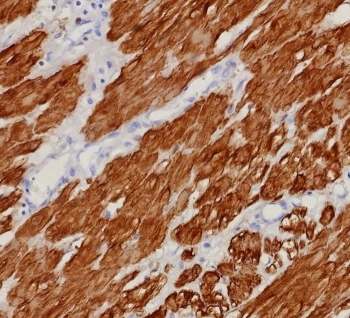

Immunohistochemistry of CNN1 Antibody in human uterus. Formalin-fixed, paraffin-embedded human uterine tissue stained with recombinant CNN1 antibody (clone rCNN1/9164) demonstrates strong cytoplasmic staining of smooth muscle cells within the myometrium, consistent with Calponin-1 expression in contractile smooth muscle fibers. Endometrial glandular epithelium shows minimal staining. Heat-induced epitope retrieval was performed by boiling tissue sections in pH 9 10mM Tris with 1mM EDTA for 20 minutes followed by cooling prior to testing.

IHC staining of FFPE human uterus tissue with CNN1 antibody (clone rCNN1/9164). HIER: boil tissue sections in pH 9 10mM Tris with 1mM EDTA for 20 min and allow to cool before testing.

CNN1 expression is characteristic of vascular smooth muscle, gastrointestinal smooth muscle, uterine smooth muscle, and myoepithelial cells of glandular tissues such as breast and salivary gland. The expected immunohistochemical pattern is cytoplasmic staining in smooth muscle layers and myoepithelial cell populations. Because of this lineage-restricted distribution, Calponin-1 serves as a reliable research marker for identifying smooth muscle and myoepithelial differentiation in normal tissues.